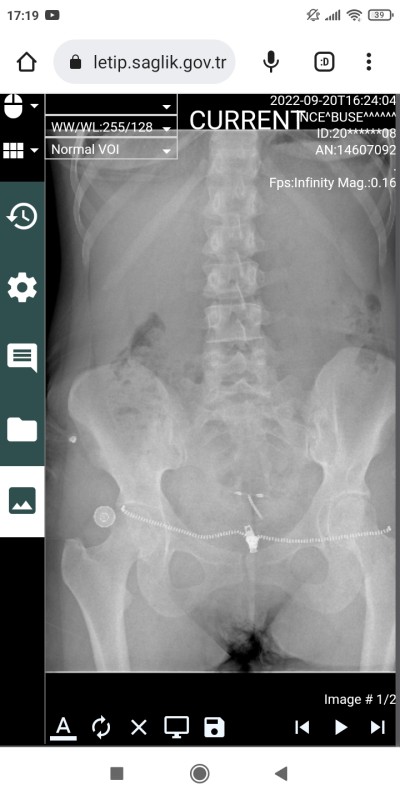

20 Eylül 2022 Doğum Sonrası Anne kategorisinde (79 puan) tarafından soruldu

Bugün acile gittim spiral için ama baştan savdilar

Konuyla alakasiz ama rontgen resmini nasil baktiniz ya

Ben hiç anlamadım nerede spiral burda